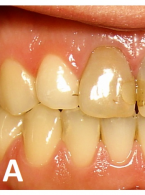

• Zastosowanie kompozytów w bezpośredniej odbudowie zębów przednich po urazie

• Bezpośrednia licówka kompozytowa w odcinku przednim wykonana z użyciem uniwersalnego kompozytu typu…